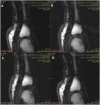

Cracking sounds emitted from human synovial joints have been attributed historically to the sudden collapse of a cavitation bubble formed as articular surfaces are separated. Unfortunately, bubble collapse as the source of joint cracking is inconsistent with many physical phenomena that define the joint cracking phenomenon. Here we present direct evidence from real-time magnetic resonance imaging that the mechanism of joint cracking is related to cavity formation rather than bubble collapse. In this study, ten metacarpophalangeal joints were studied by inserting the finger of interest into a flexible tube tightened around a length of cable used to provide long-axis traction. Before and after traction, static 3D T1-weighted magnetic resonance images were acquired. During traction, rapid cine magnetic resonance images were obtained from the joint midline at a rate of 3.2 frames per second until the cracking event occurred. As traction forces increased, real-time cine magnetic resonance imaging demonstrated rapid cavity inception at the time of joint separation and sound production after which the resulting cavity remained visible. Our results offer direct experimental evidence that joint cracking is associated with cavity inception rather than collapse of a pre-existing bubble. These observations are consistent with tribonucleation, a known process where opposing surfaces resist separation until a critical point where they then separate rapidly creating sustained gas cavities. Observed previously in vitro, this is the first in-vivo macroscopic demonstration of tribonucleation and as such, provides a new theoretical framework to investigate health outcomes associated with joint cracking.